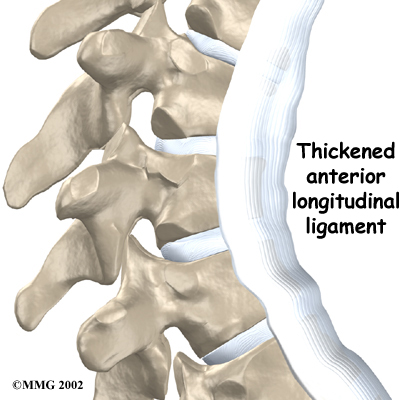

A long ligament called the anterior longitudinal ligament connects on the front of the vertebral bodies. This ligament typically thickens in patients with Scheuermann's disease and adds to the forward pull on the spine, producing more wedging and kyphosis.